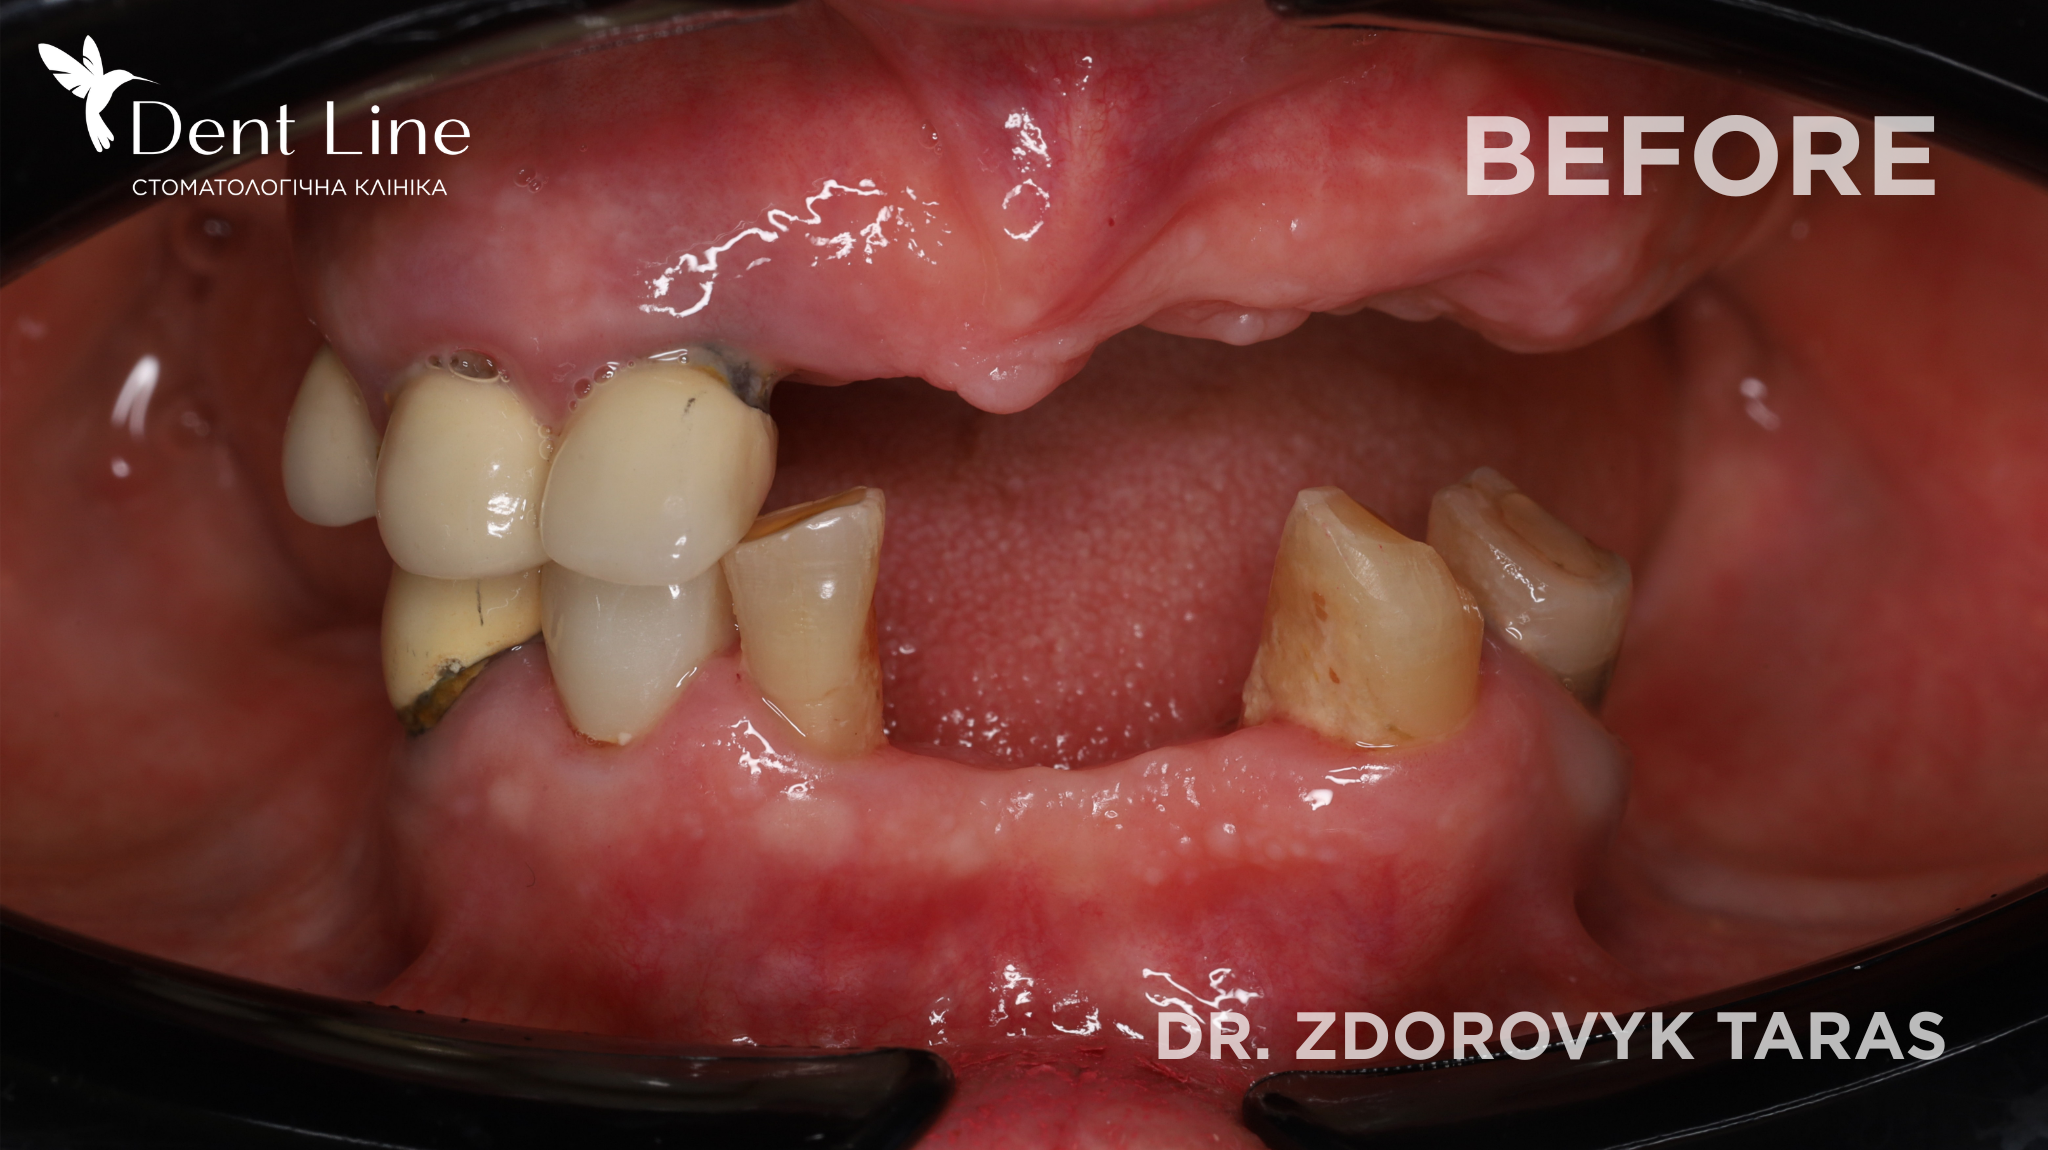

Пацієнтка звернулась до нас зі скаргами на втрату зубів внаслідок карієсу та його ускладнень, неможливість повноцінно пережовувати їжу та виражений естетичний дефект. Було проведено імплантацію за методикою All-on-4 — встановлення імплантів JDental на верхній та нижній щелепі з негайним навантаженням. Операцію виконано в один день. У день втручання пацієнтка отримала тимчасові ортопедичні конструкції, що дозволило одразу відновити естетику посмішки та функцію жування.

Після повного загоєння імплантів тимчасові конструкції будуть замінені на постійну ортопедичну роботу.